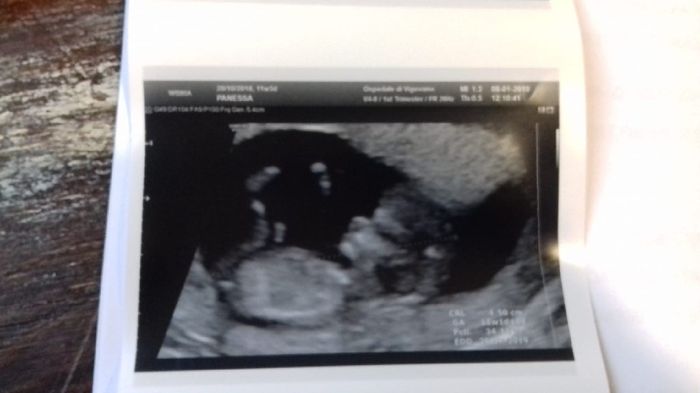

Già lo amoooo

Ma quanto è bello/a il mio piccolino/a? È stata un'emozione unica😍😍😍 Ora a marzo ci diranno se è maschio o femmina.. mio marito dice che già dalla foto si vede che è un...